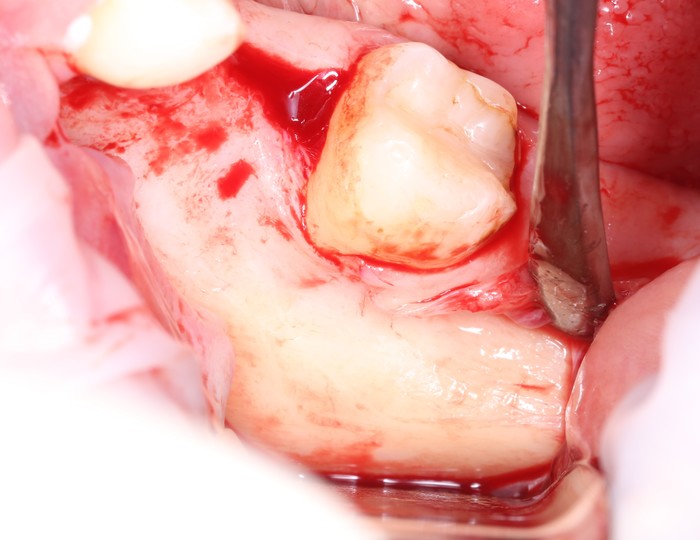

Скелетирование кости:

При помощи ультразвукового наконечника выделяется костный фрагмент,

а специальных остеотомов – отделение этого фрагмента от челюсти:

Остеотом необходимого размера помещается в щель, сделанную ультразвуковым наконечником, а дальше производится расклинивание.